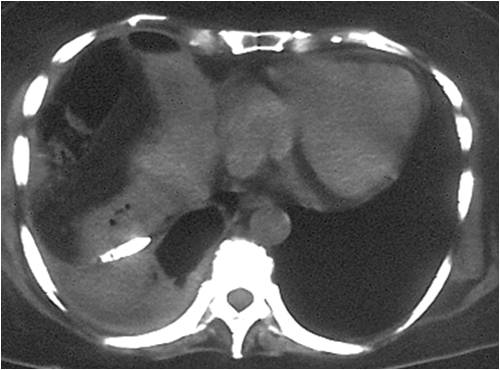

- Large abdominal abscess post- pancreatic surgery

- Successful drainage